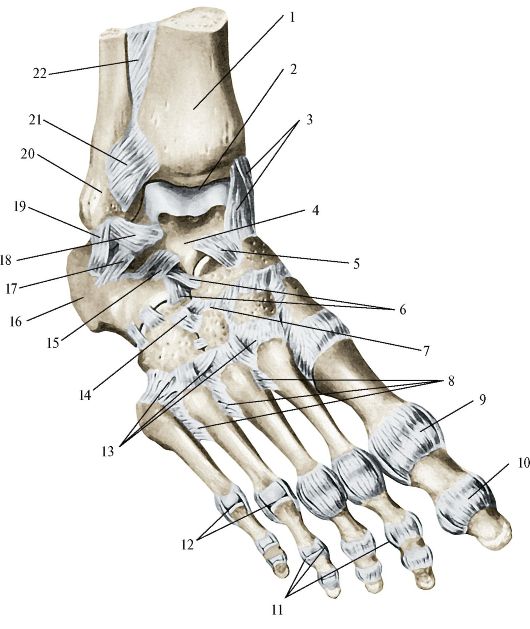

Анатомические фото голеностопного сустава и его суставных поверхностей